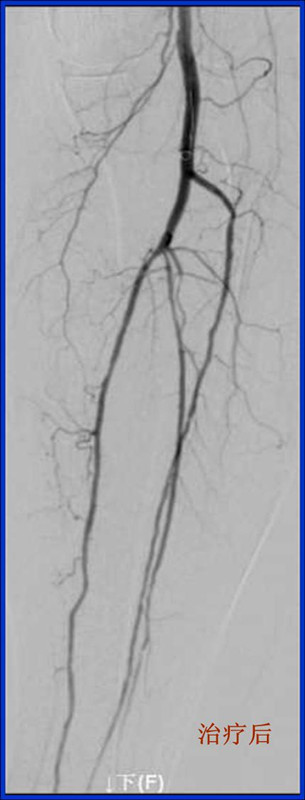

8月26日下午,我院中医外科叶海东医生和心内科潘兴丰医生合作,在放射科和手术室人员的协助配合下,成功完成了2例下肢动脉造影+球囊扩张术。据悉,这是我院首次完成血管腔内介入手术。